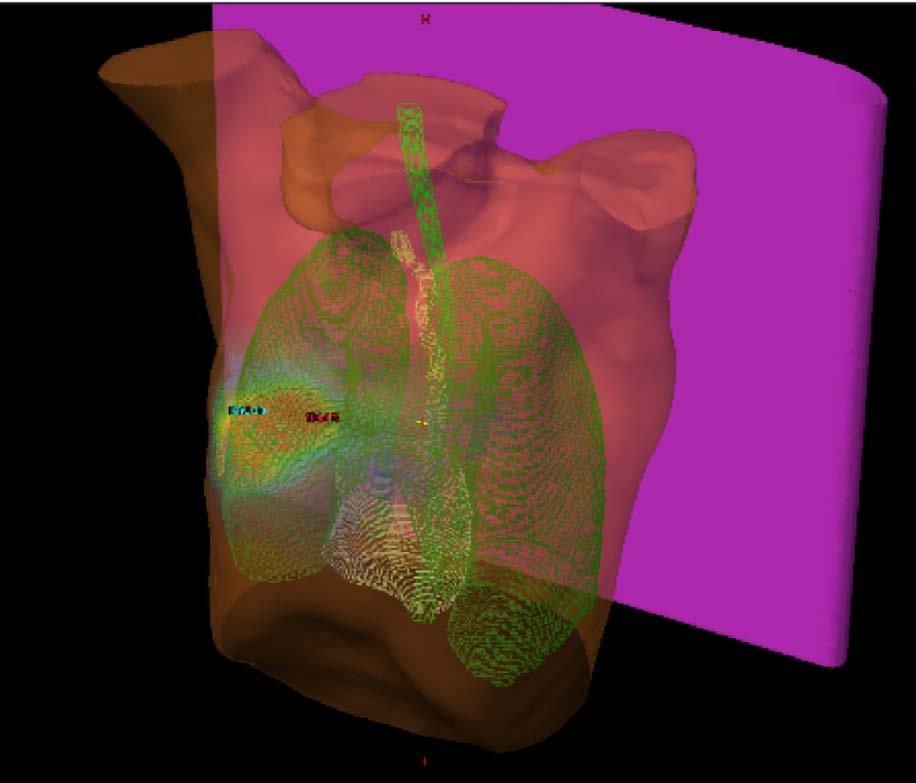

Á síðastliðnum tveimur áratugum hafa orðið miklar framfarir í greiningu lungnakrabbameins, ekki síst með tilkomu jáeindaskanna og berkjuómspeglunar, sem hafa bætt stigun sjúkdómsins og gert meðferð markvissari. Sömuleiðis hafa orðið miklar framfarir í meðferð sjúkdómsins, ekki síst með tilkomu skurðaðgerða þar sem notast er við brjóstholssjá sem stytt hafa legutíma og fækkað fylgikvillum. Sömuleiðis nýtist hnitmiðuð geislameðferð oftar sjúklingum sem ekki er treyst í skurðaðgerð. Mestar hafa framfarirnar þó orðið í meðferð útbreidds lungnakrabbameins, ekki síst með tilkomu öflugra líftækniog ónæmishvetjandi lyfja sem nota má til að klæðskerasauma meðferð út frá mælingum á stökkbreytingum og lífmörkum í æxlunum.